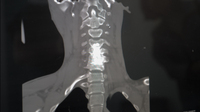

Після огляду пацієнта та обстеження за допомогою магніторезонансної та комп'ютерної томографії, виявили рідкісну хронічну рецидивуючу інфекцію, пов'язану з імплантом, - розповіли на сторінці Тернопільської міської комунальної лікарні швидкої допомоги у фейсбуці. - З урахуванням усіх даних прийнято рішення провести більш радикальну операцію з видалення інфікованого імпланту та висічення всіх нежиттєздатних тканин.

Хірургічне втручання було складним і тривалим через змінену нормальну анатомію шиї та рубці від численних попередніх операцій. За допомогою спеціалізованих інструментів медикам вдалось виконати доступ, ідентифікувати межі інфекції, висікти інфіковані тканини й видалити імплант, зберігши консолідовані ділянки кістки, що дозволило зберегти форму та висоту хребця.